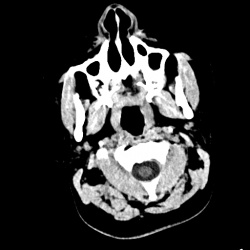

Мужчина 30 лет, получил удар в глазную область слева 2 недели назад, это ведь переломы решетчатой кости и нижней стенки глазницы? а в пазухе это кровь?